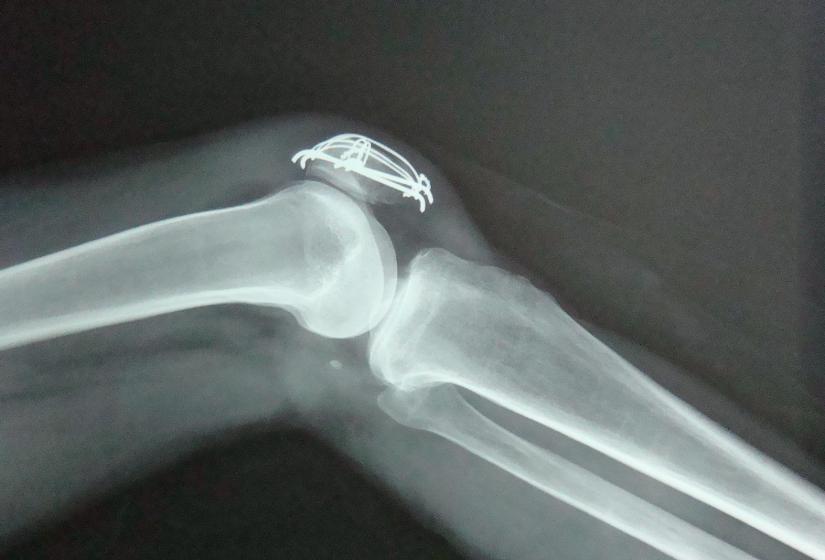

积液量比较少的,不需要抽取关节液。积液量比较大的(超过50毫升),要做关节穿刺抽液,抽液后还要给膝关节加压包扎,防止再次积液。